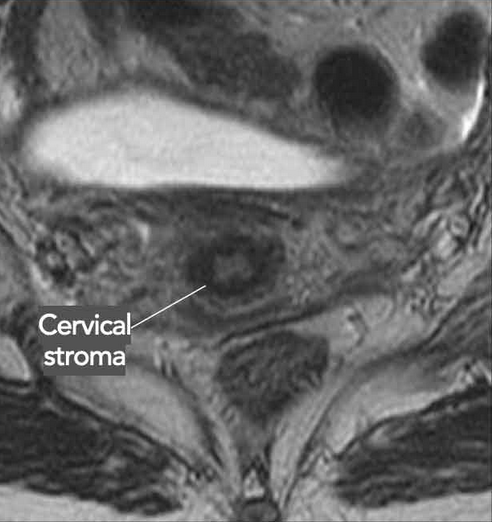

• 2B - Tumor invasion beyond the uterus with para-metrial invasion (basically dark circular border of cervix) - see image —>